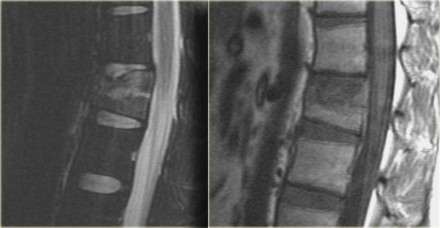

Jumper's fracture

On the left a fracture of the calcaneus and a lumbar spine fracture.

This is called a 'jumpers fracture' or a 'lover's fracture', because it

is usely seen in people jumping out of a window to escape from the

police or a jealous husband.

In this case it is clear that we are looking at an unstable fracture, because this is a burst fracture.

Both the anterior and the middle column are disrupted.

In addition there is edema in the posterior soft tissues indicating that there is also involvement of the posterior column.

Notice also the marrow edema in the adjacent bodies due to the severe axial loading.